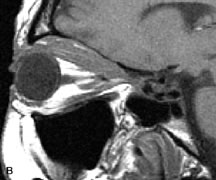

On MRI, uveal melanomas have a typical appearance that helps to differentiate them from other primary and secondary intraocular tumors as well as choroidal detachments. Pigmented melanomas are hyperintense on Tl-weighted images, hypointense on T2-weighted studies, and hyperintense on proton density–weighted examinations (Fig. 24).30,31,50,80–82 These signal characteristics have been attributed to the paramagnetic properties of melanin because of stable free radicals that shorten the T1 and T2 relaxation times. Moderate enhancement is seen on postgadolinium T2-weighted images. Gadolinium-enhanced T1-weighted images are particularly sensitive in detecting choroidal melanomas.83 MRI may be less sensitive in detecting extrascleral extension of tumor than echography performed by an experienced ultrasonographer.84

Fig. 24. A. T1- and (B) T2-weighted MR scans demonstrate a small nodular intraocular mass (arrows) that is very hyperintense on the T1-weighted scan and hypointense on the T2-weighted image. This signal intensity pattern is due to the presence of free radicals within melanin granules. C and D. Postcontrast fat-suppressed T1-weighted scans demonstrate homogeneous intense enhancement of the lesion and no evidence of seleral penetration or optic nerve invasion.